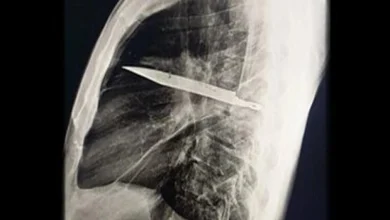

مردی که ۸ سال با این چاقو در بدنش زندگی میکرد!

در یک مورد نادر پزشکی یک مرد ۴۴ ساله اهل کشور تانزانیا پس از اینکه با ترشح چرک از قفسه…